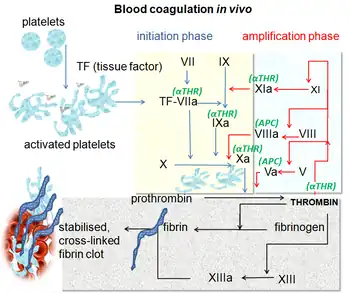

Blood has a natural tendency to clot when blood vessels are damaged (hemostasis) to minimize blood loss.[102] Clotting is activated by the coagulation cascade and the clearing of clots that are no longer needed is accomplished by the process of fibrinolysis. Reductions in fibrinolysis or increases in coagulation can increase the risk of DVT.[102]

In arterial thrombosis, blood vessel wall damage is required, as it initiates coagulation,[108] but clotting in the veins mostly occurs without any such mechanical damage.[62] The beginning of venous thrombosis is thought to arise from "activation of endothelial cells, platelets, and leukocytes, with initiation of inflammation and formation of microparticles that trigger the coagulation system" via tissue factor.[77] Vein wall inflammation is likely the inciting event.[77] Importantly, the activated endothelium of veins interacts with circulating white blood cells (leukocytes).[55] While leukocytes normally help prevent blood from clotting (as does normal endothelium), upon stimulation, leukocytes facilitate clotting.[109] Neutrophils are recruited early in the process of venous thrombi formation.[55] They release pro-coagulant granules[109] and neutrophil extracellular traps (NETs) or their components, which play a role in venous thrombi formation.[55][110] NET components are pro-thrombotic through both the intrinsic and extrinsic coagulation pathways.[110] NETs provide "a scaffold for adhesion" of platelets, red blood cells, and multiple factors that potentiate platelet activation.[111] In addition to the pro-coagulant activities of neutrophils, multiple stimuli cause monocytes to release tissue factor.[109] Monocytes are also recruited early in the process.[55]

Tissue factor, via the tissue factor–factor VIIa complex,[112] activates the extrinsic pathway of coagulation and leads to conversion of prothrombin to thrombin, followed by fibrin deposition.[86] Fresh venous clots are red blood cell and fibrin rich.[42] Platelets and white blood cells are also components. Platelets are not as prominent in venous clots as they are in arterial ones, but they can play a role.[56] In cancer, tissue factor is produced by cancer cells.[84] Cancer also produces unique substances that stimulate factor Xa, cytokines that promote endothelial dysfunction, and plasminogen activator inhibitor-1, which inhibits the breakdown of clots (fibrinolysis).[84]

Often, DVT begins in the valves of veins.[105] The blood flow pattern in the valves can cause low oxygen concentrations in the blood (hypoxemia) of a valve sinus. Hypoxemia, which is worsened by venous stasis, activates pathways—ones that include hypoxia-inducible factor-1 and early-growth-response protein 1. Hypoxemia also results in the production of reactive oxygen species, which can activate these pathways, as well as nuclear factor-κB, which regulates hypoxia-inducible factor-1 transcription.[86] Hypoxia-inducible factor-1 and early-growth-response protein 1 contribute to monocyte association with endothelial proteins, such as P-selectin, prompting monocytes to release tissue factor-filled microvesicles, which presumably begin clotting after binding to the endothelial surface.[86]